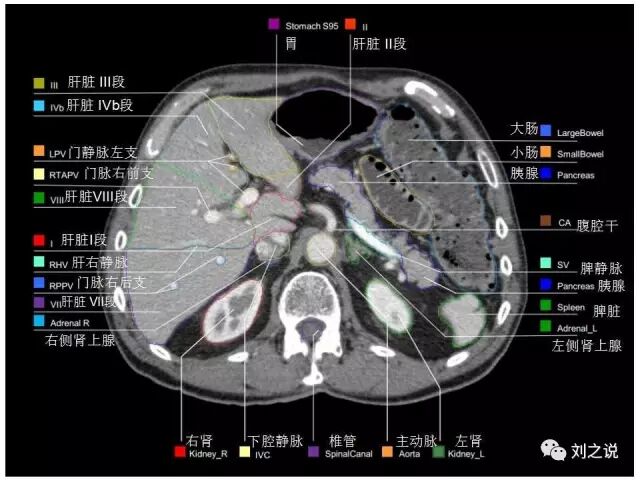

【解剖】高清实用 腹部CT断层

参考RTOG共识和3D-body解剖。

5.上腹部CT断层 (肝脏解剖及肝段分布、腹部淋巴结分布)